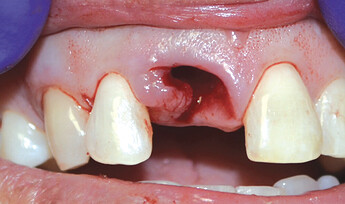

The patient presented with a failing tooth #8. After extraction, the socket shape resembled a triangle. Because of the round shape of the dental implant, there were gaps between the implant body and the alveolus which required grafting.

After the tooth was extracted, the site was thoroughly curetted. A pilot drill was used to begin the osteotomy, which was enlarged to the correct size for the implant. Prior to placing the implant, OsteoGen strip alloplast was re-hydrated with sterile saline and then placed in the socket against the wall adjacent to the gap. Hahn™ Tapered Implant (Glidewell Direct; Irvine, Calif.) was driven into place, and the graft material filled the gap. A healing abutment was placed and the site sutured with a Reli® REDISORB® PRO PGA 4-0 suture.